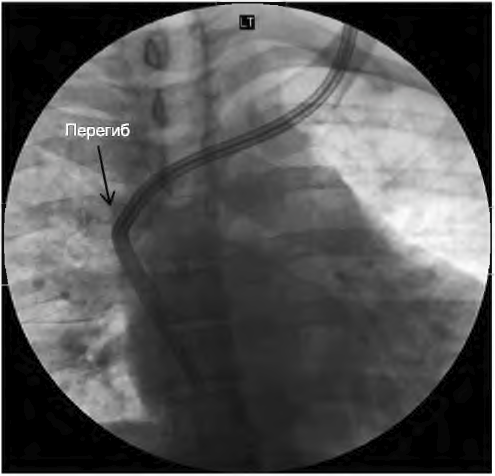

А. Начальная дисфункция. Недавно установленные катетеры могут давать плохой кровоток из-за перегиба, сдавления катетера внутри туннеля отеком, неправильного положения катетера (в непарной или полунепарной вене) или неправильного расположения кончика катетера (рис. 9.3). Для диагностики полезна рентгенография. Отек в туннеле обычно разрешается за 24 часа. Наличие перегиба или неправильного расположения кончика катетера требует его перестановки с созданием другого туннеля или использования другой длины катетера. Важно также устанавливать катетер в нижней части шеи близко к ключице; высокое расположение катетера на шее может сделать катетер «позиционным», с кровотоком, зависящим от положения шеи. Фактически кончик катетера поднимается при наклоне шеи, приводя к плохому кровотоку. Место выхода близко к молочной железе может также тянуть кончик катетера вверх, в верхнюю полую вену. Экструзия муфты в результате перемещения катетера или эрозия тканей повышают риски дисфункции и инфекции. Такие катетеры требуют замены.

РИСУНОК 9.3. Перегиб: катетер в левой яремной вене с перегибом

Если в туннеле есть эрозия или он инфицирован, требуется создание нового туннеля или новое место установки. Катетеры в левой яремной вене характеризуются большей частотой дисфункции, чем в правой (Engstrom, 2013), по не вполне понятным причинам, возможно, из-за извилистого пути до входа в правое предсердие.